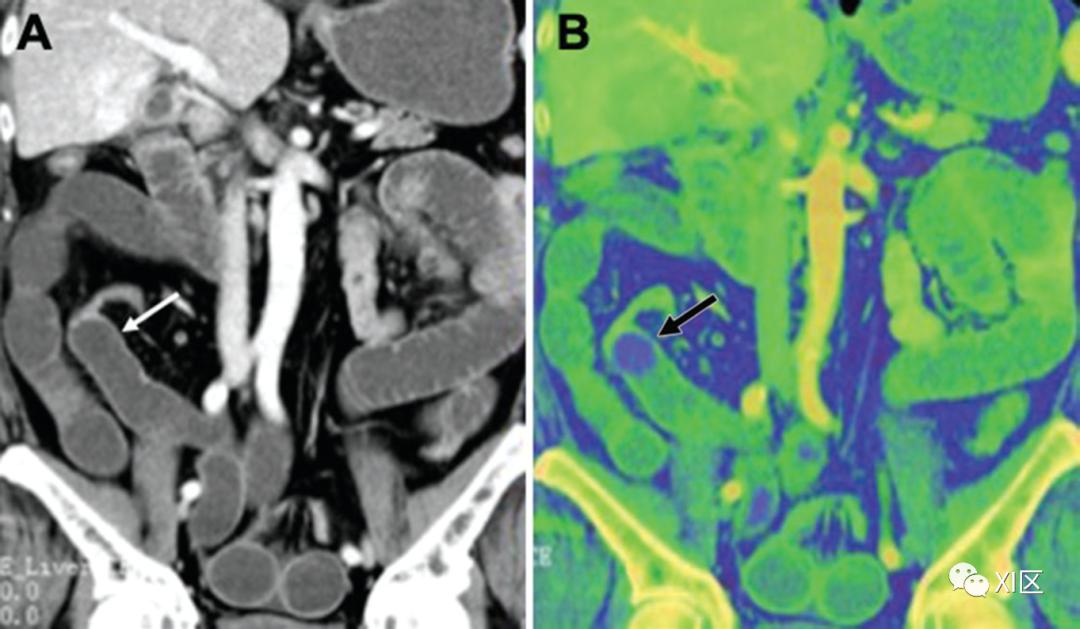

在碘图上,胃和结肠肿瘤的可检测性得到了改善(图15),恶性和良性病变的鉴别也得到了改善。碘图像也适用于急腹症患者,如小肠缺血或胃肠道出血。它们增加肠壁低衰减段的显著性,从而潜在地改善缺血的早期检测。它们还可以帮助识别造影剂外渗的细微区域,以便准确定位胃肠道出血的来源。

图15 71岁男性患有升结肠癌。显示了动脉期70 keV(a)下的虚拟单色图像和碘图(b)。碘图比单色70keV图像更显眼。(c)PET-CT图像(肿瘤的最大标准化摄取值为6.1)增强双能量CT扫描对于血管内主动脉修复术(EVAR)后的内漏检测有价值。在较低能量下获得的VMI会增加血管对比度,而晕染和金属伪影会降低图像质量。另一方面,碘图在不增加晕影的情况下提高了内漏的显著性(图16)。